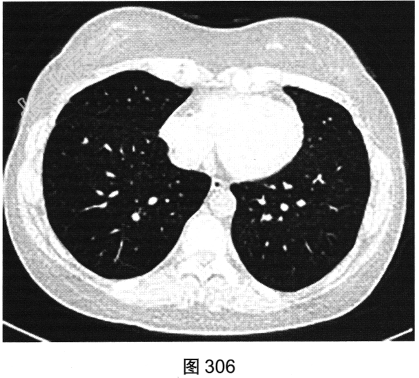

- [材料题] 患者女性,32岁,因“间断刺激性干咳1年,发现肺部囊性病变8个月”就诊。患者无发热、咯血、胸痛、呼吸困难。服甘草片、阿莫西林无明显好转。胸部HRCT如图302~图307所示。

- 多项选择题1.患者胸部HRCT的阳性征象有( )

- 多项选择题2.影像检查所示肺内主要病变的形态、分布特点为( )

A、囊状透亮影形状不规则、大小不一

C、囊状透亮影形状规则,大小及肺内分布均匀

G、囊壁较薄、略欠均匀,部分囊壁欠连续